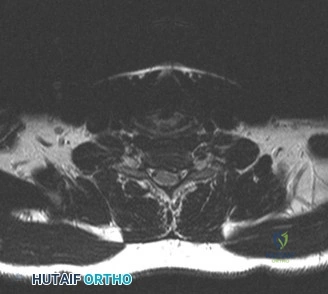

To contextualize the decision-making algorithm, consider the classic presentation of a middle-aged patient with multiple medical comorbidities. A paradigmatic case involves a 48-year-old obese female (Body Mass Index of 43) with poorly controlled diabetes mellitus who presents with severe, unrelenting low back pain, fevers, and chills. Advanced imaging, specifically magnetic resonance imaging (MRI), typically demonstrates discitis involving the L4–5 disc space with adjacent osteomyelitis of the L4 and L5 vertebral bodies. Crucially, in many early or medically responsive cases, there is an absence of epidural abscess formation, and standing radiographs reveal relatively normal sagittal and coronal alignment. When such a patient is neurologically intact—lacking saddle anesthesia, bowel/bladder incontinence, or upper motor neuron signs—the immediate clinical imperative shifts from urgent surgical decompression to aggressive pathogen identification and targeted antimicrobial therapy.

Pre-Operative Planning, Templating, and Patient Positioning

When surgical intervention becomes unavoidable, meticulous pre-operative planning is the cornerstone of a successful outcome. Advanced imaging is non-negotiable. An MRI with and without gadolinium contrast is the gold standard for defining the extent of the epidural abscess, the degree of neural compression, and the involvement of adjacent paraspinal musculature (e.g., psoas abscess). T1-weighted images typically show hypointense signals in the infected marrow, while T2-weighted and STIR sequences reveal hyperintense fluid and edema in the disc space and vertebral bodies. Gadolinium enhancement highlights the vascularized inflammatory phlegmon and the capsule of any abscesses.